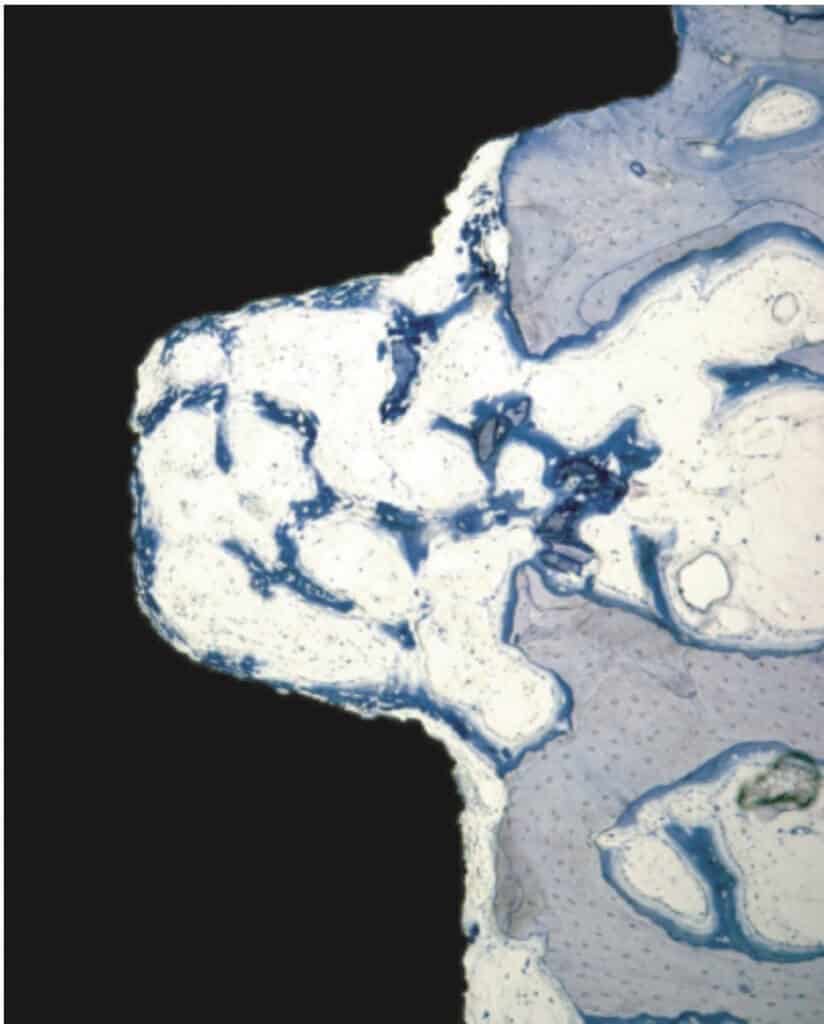

Right after implant placement, friction stability was achieved thanks to the pitches of the threads biting tight into the bone walls, while the non-contact areas filled with blood clot. The big news came however on the 4th day, when an interesting pattern of bone resorption occurred at the coronal side of the pitch! Why resorption? Obviously the compression of the bone there had killed a zone of bone about 50 μm, which was now being cleared away.

Back to our histology study, the observation of the 4th day was actually an “aha” moment for all. It showed how compression kills bone and initiates resorption early after placement. This observation seen however in isolation made many clinicians to blame extensive threads as “bone killers”, starting the perception of implants with shallow or few threads as being “passive”. (It was also probably the reason why this experimental implant remained forever a dog-implant).

To get the whole picture, we need to look closer at the other side of the coin and see what happens in the no-contact areas. There, at 1 week one could see another exciting development: contact osteogenesis! New mineralized bone was created on the surface of the implant in the empty chamber, where previously only blood clot existed. This was something hardly seen on the smooth surface implants, but was apparent in the SLA implants introducing another factor in the equation, the implant surface.

The collective message of these amazing experiments was the while bone is being cleared at the pitch of the thread, new bone is getting created on the implant surface at the no-contact areas! Surface is a significant factor here, with contact osteogenesis being well established at 2 weeks in humans with SLAactive implants, as documented by another great study by Lang et al (4). Lang as well, noted absence of new bone at the pitch of the thread after 1 week, but significant new bone in non-contact areas, where the “jumping” distance between the implant and the bone was short. Again, this message seen somewhat superficially, lead many to believe that the lower and fewer the implant threads, the better the implant would be, reinforcing the anecdotal concept of “aggressive” and “passive” implants. But as you can’t judge a book by its cover, you shouldn’t also judge an implant by its threads! The missing part here was that an implant with few and shallow threads will be unlikely to offer adequate primary stability!